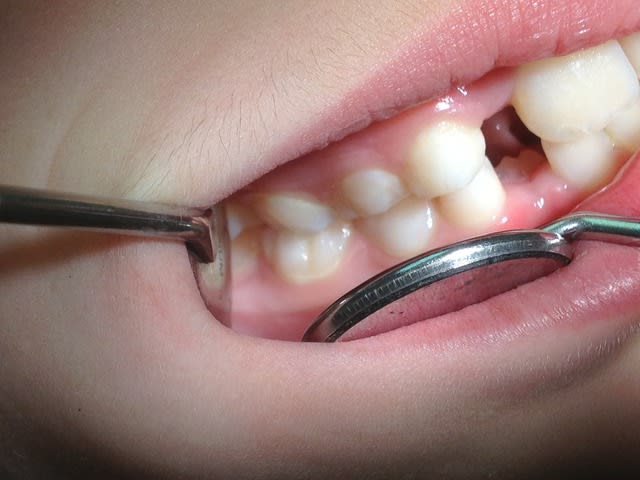

Re!! voila quelques photos,et que pensez vous de l'ortho qui pense que l'expansion n'est pas possible car il ne s'agit pas d'une endoalveolie??Merci

On ne peut pas dire grand chose avec ces photos, tu nous donnes des photos et des radios du secteur antérieur pour qu'on te donne un avis sur ce qui se passe en postérieur... Ce qui aurait été intéressant ça aurait été de voir la forme du palais par exemple ou au moins l'occlusion sur les secteurs latéraux.

Bref, pour faire simple, là on voit pas grand chose, mais j'ai l'impression sur ta 4eme photo que l'occlusion est inversée à droite... 85 semble plus vestibulaire que son antagoniste, non ? Et du peu qu'on en voit en secteur gauche ça semble être du même genre non ? Regarde la forme du palais : s'il te semble creusé et étroit, ça doit te mettre la puce à l'oreille.